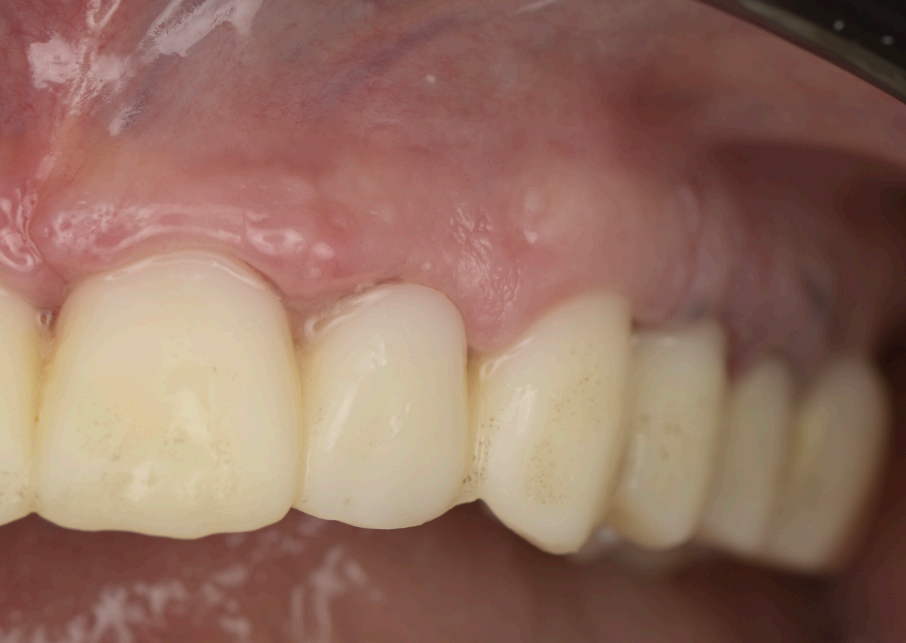

Preoperative and Planning •Fig. 1.1: Frontal intraoral view of the maxilla showing residual roots and fractured teeth. •Fig. 1.2: Occlusal intraoral view highlighting the compromised dentition. •Fig. 1.3: Digital wax-up integrated with a 3D facial scan and smile design guidelines. •Fig. 1.4, 1.5: Visualization of implant positions (16, 14, 12, 22, 24, 26) on a 3D model, prosthetically driven placement. •Fig. 1.6: 3D rendering of the wax-up aligned with the bone level, illustrating bone-prosthesis relationship.

The patient, a 70-year-old female, presented to the dental clinic with a chief complaint of compromised maxillary dentition and a desire for a fxed, aesthetically pleasing rehabilitation. Her medical history was unremarkable, with no systemic diseases, allergies, or medications reported, and her general health was deemed excellent for her age. Intraoral examination revealed a partially edentulous maxilla with failing dentition: residual roots were present at positions 13 (upper right canine) and 21 (upper left central incisor), while teeth 22 (upper left lateral incisor) and 13 exhibited fractures rendering them non-restorable (Fig. 1.1, 1.2). The patient expressed a strong preference for a fxed prosthesis that would restore both function and aesthetics, with a natural gingival contour as a priority.